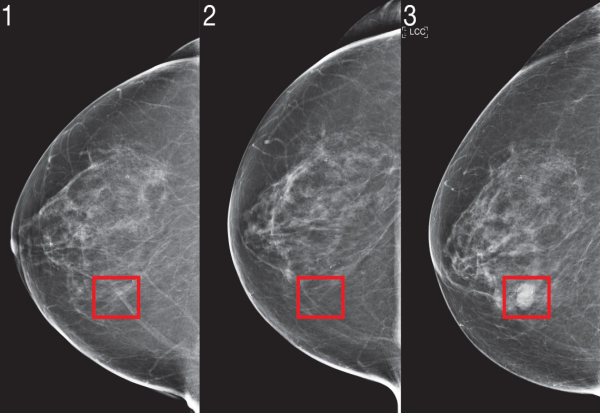

Алгоритамот ги анализирал и претходните мамограми и се чини дека функционира дури и кога лекарите не ги гледаат знаците на предупредување во претходните скенирања.

Фото: MIT

Алгоритамот ги анализира стандардните четири прегледи со мамограф, од кои потоа донесува заклучоци за пациентот, како историја на операции или хормонски фактори, како што е менопаузата. Ова може да помогне ако тие податоци претходно не се знаеле.

Откриено е дека „Мираи“ е попрецизен од статистичките модели кои обично се користат за проценување на ризикот од рак на дојка кај жените. Јала вели дека моделот генерализира добро поради големата, доволно разновидна база на податоци што ја користи, но забележува дека секогаш е важно да се потврдат алгоритмите во различни поставки.